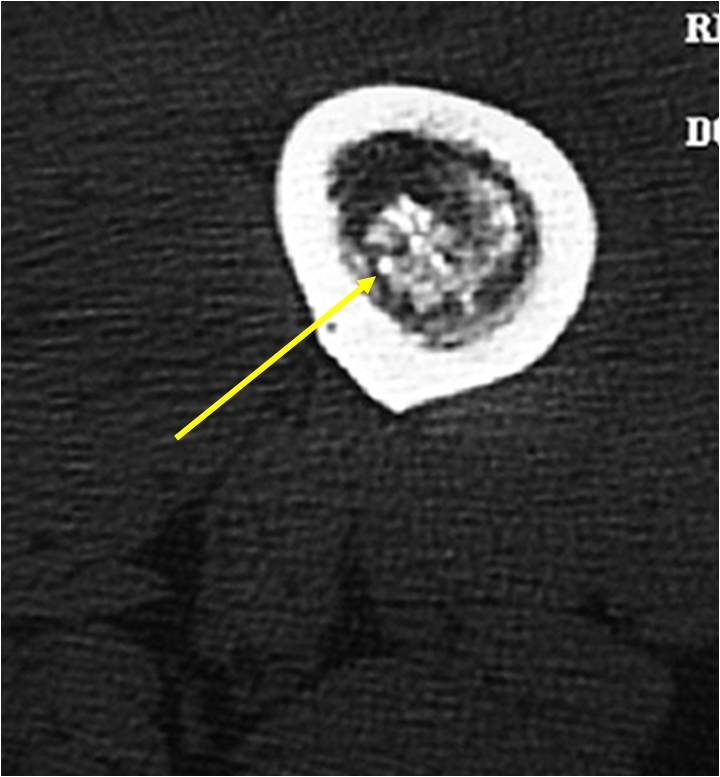

MRI:

- Lobulated margin (Lobular Growth Pattern)

- T1 Weighted Images: Intermediate Signal Intensity

- Calcifications will be low signal

- T2 Weighted Images: High Signal Intensity

- High water content shows as high signal on T2 weighted images

- Marked increased intensity long TR images

- Calcified chondroid – low intensity all sequences

- There should never be any cortical destruction nor a soft tissue component. If this exists then the tumor must be a chondrosarcoma.

- Endosteal scalloping and cortical expansion is acceptable for phalangeal tumors. In most benign long bone cartilage tumors there is minimal endosteal scalloping but there should be no cortical expansion nor thickening. There should be no cortical destruction and no soft tissue component associated with an enchondroma. Cortical destruction, periosteal thickening, cortical expansion and a soft tissue component indicates a chondrosarcoma of the long bone.

T2: High Signal No Soft Tissue Component

T1: Intermediate Signal Lobular Growth